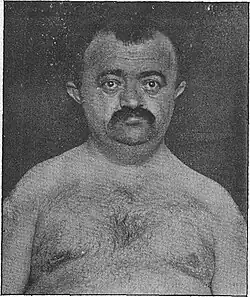

| Adult male patient described by Marie and Sainton, 1898 | |